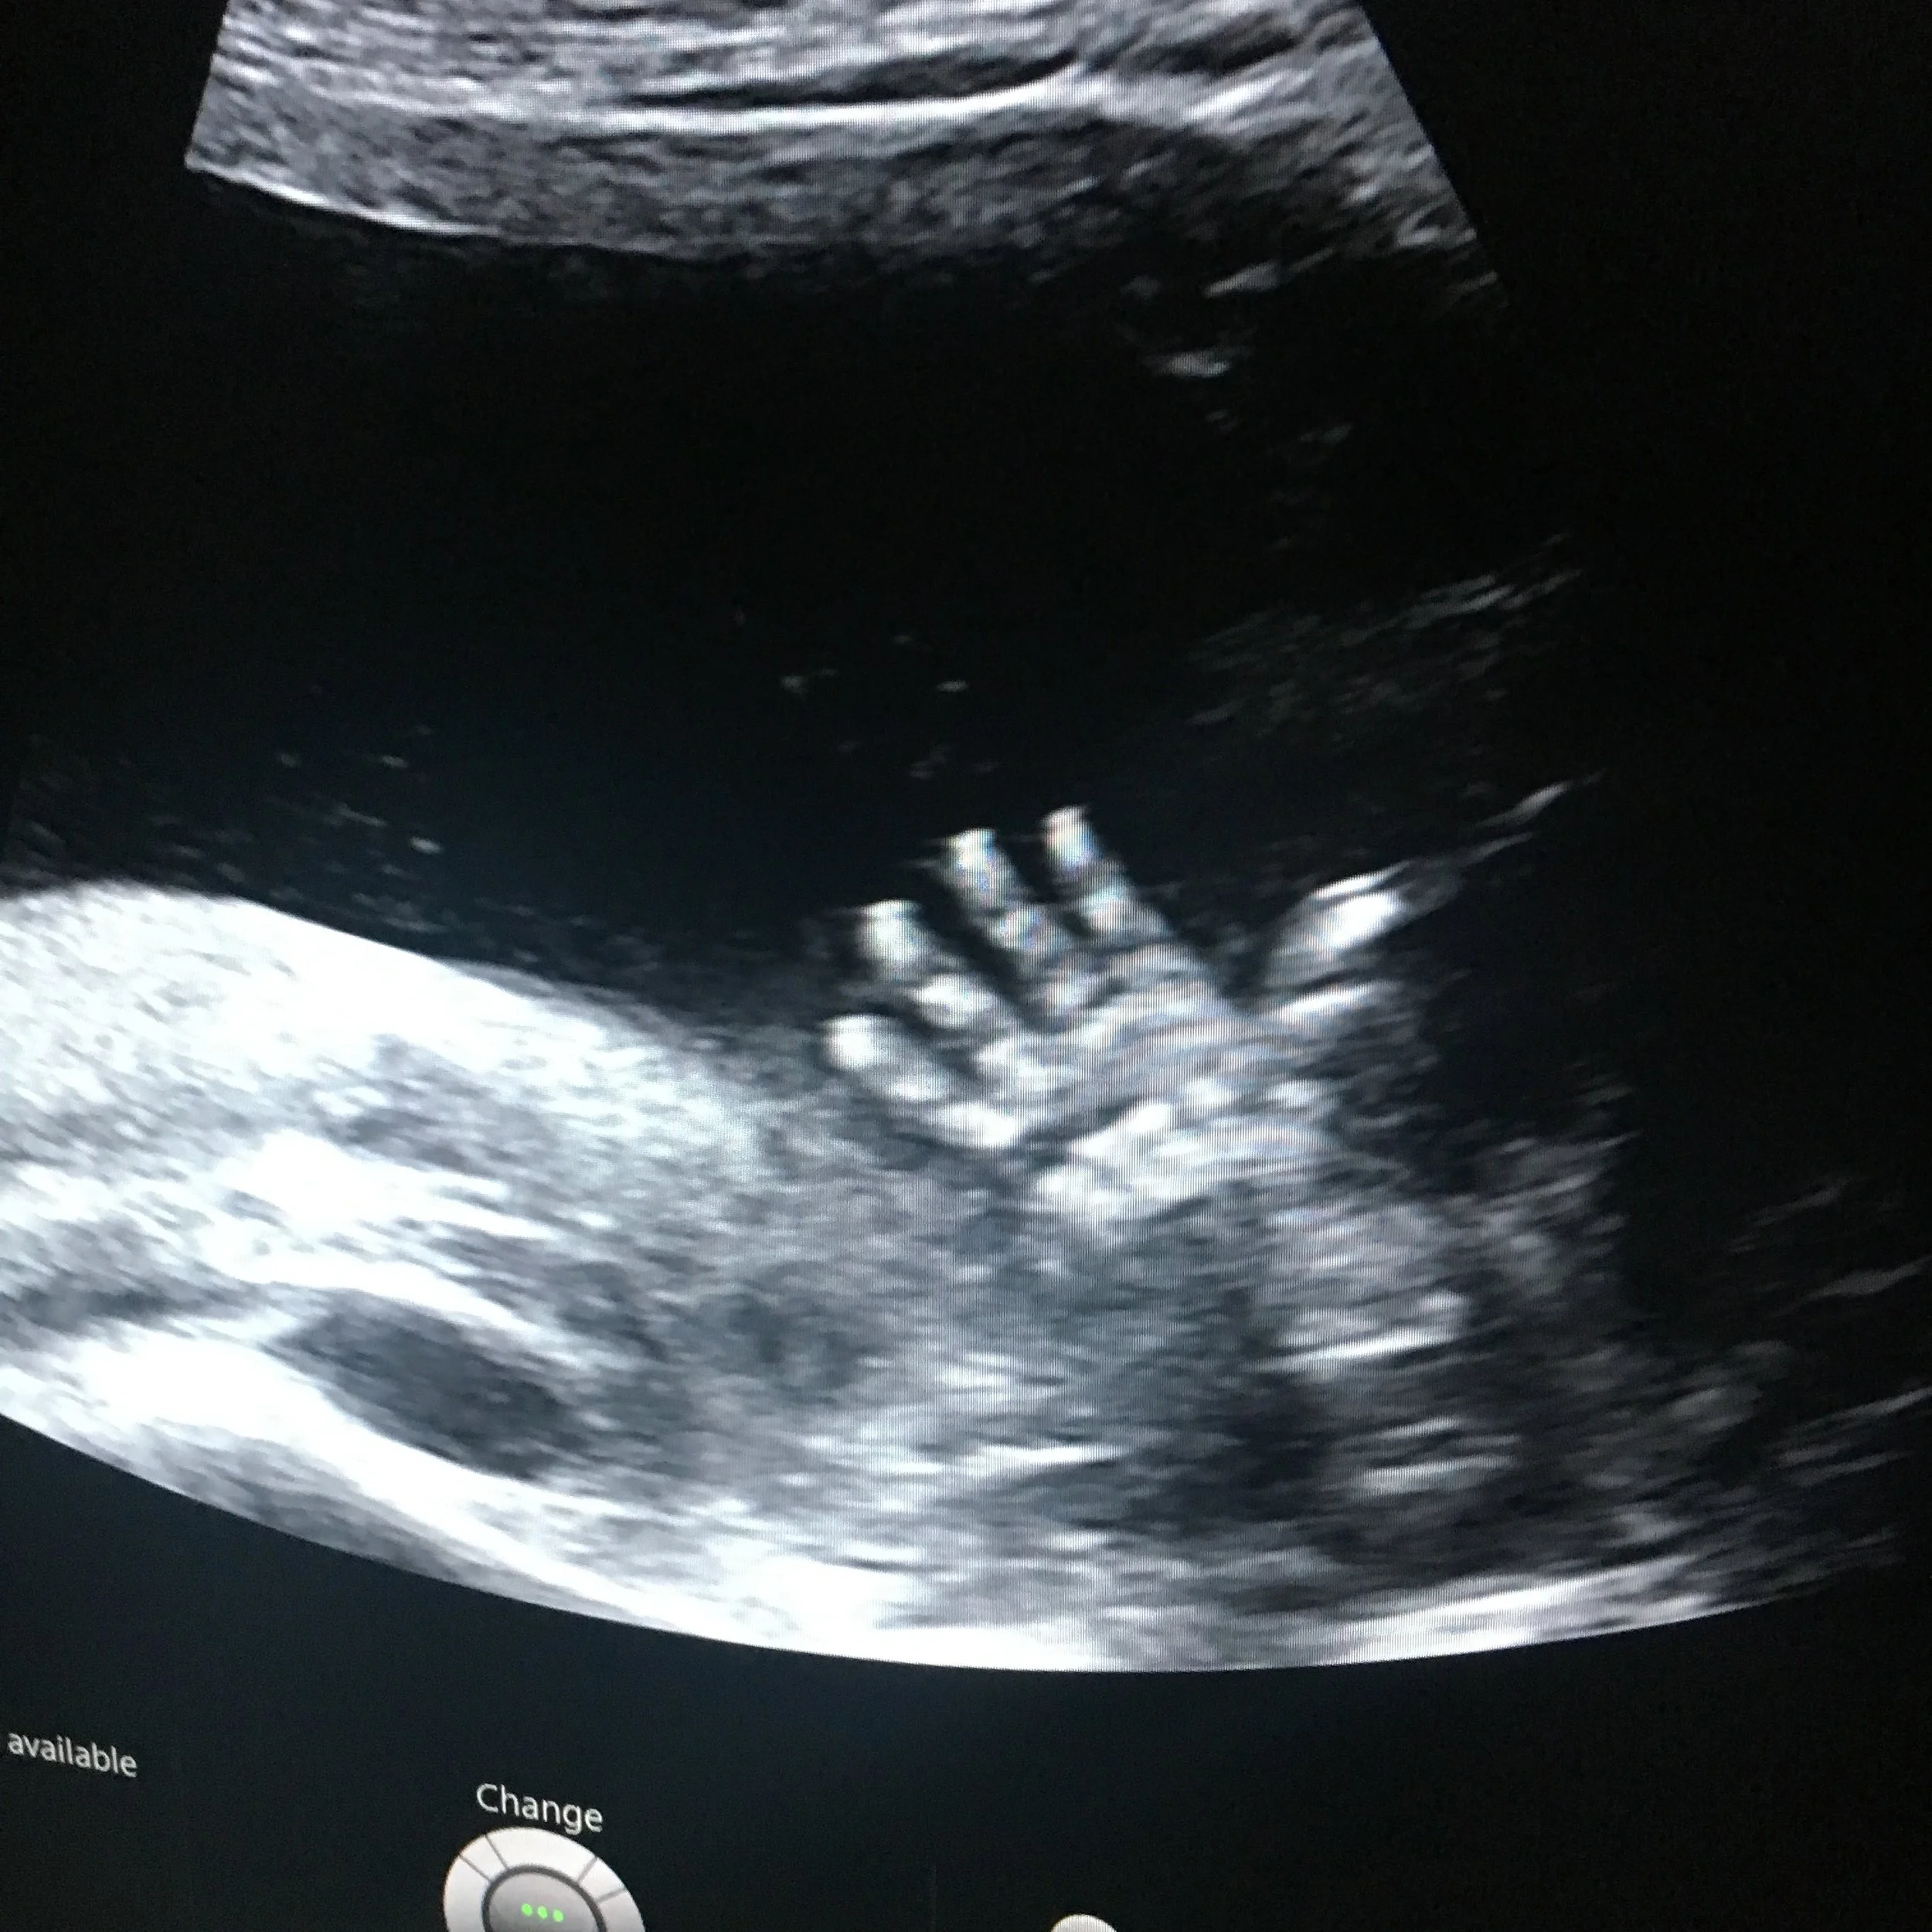

Maybe Baby #3: When the ground gives way

In this moment I had no choice. It became immediately obvious how much I wanted to be a Dad, and the extent to which I’d already allowed myself to enter into the reality of love for a child that was no longer going to find its way into the world. I sobbed uncontrollably for over an hour. Waves and waves of grief and emotion pulsing through my body beyond my control. I’ve never experienced anything like it. It was primal anguish and grief, it was years of disappointment that had been overcome in joy and then cruelly taken away in an instant. It was as though the ground gave way beneath my feet. Hannah arrived home and we wept together; something I don’t think we’d ever done before – not with me joining in anyway.